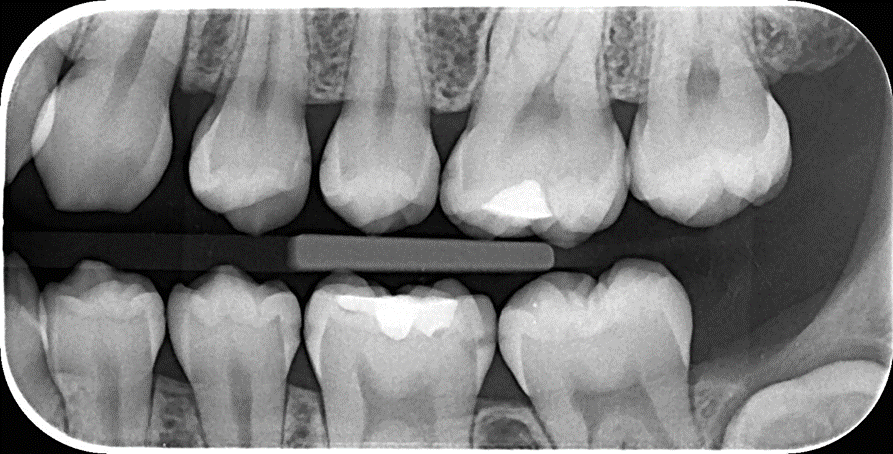

Descriere

Permit detectarea cariilor incipiente în zonele interdentare, a cariilor de colet de dimensiuni mici și localizate subgingival, a cariilor apărute sub obturații (recidivă de carie).

De asemenea, pot fi decelate leziunile osoase precoce în parodontopatii marginale, precum și procese calcifiate în camera pulpară.